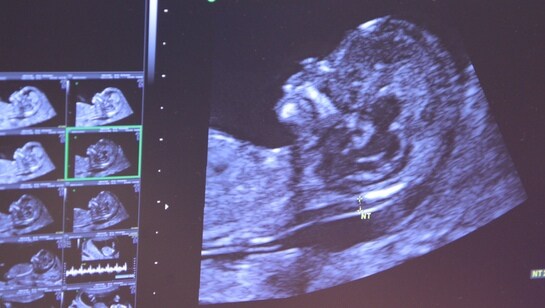

Hele 85 prosent av gravide har tatt ultralyd tidlig i svangerskapet, viser en ny undersøkelse fra Rikshospitalet. – De som har ressurser skaffer seg et bedre tilbud enn de som ikke har det, mener professor i fostermedisin.